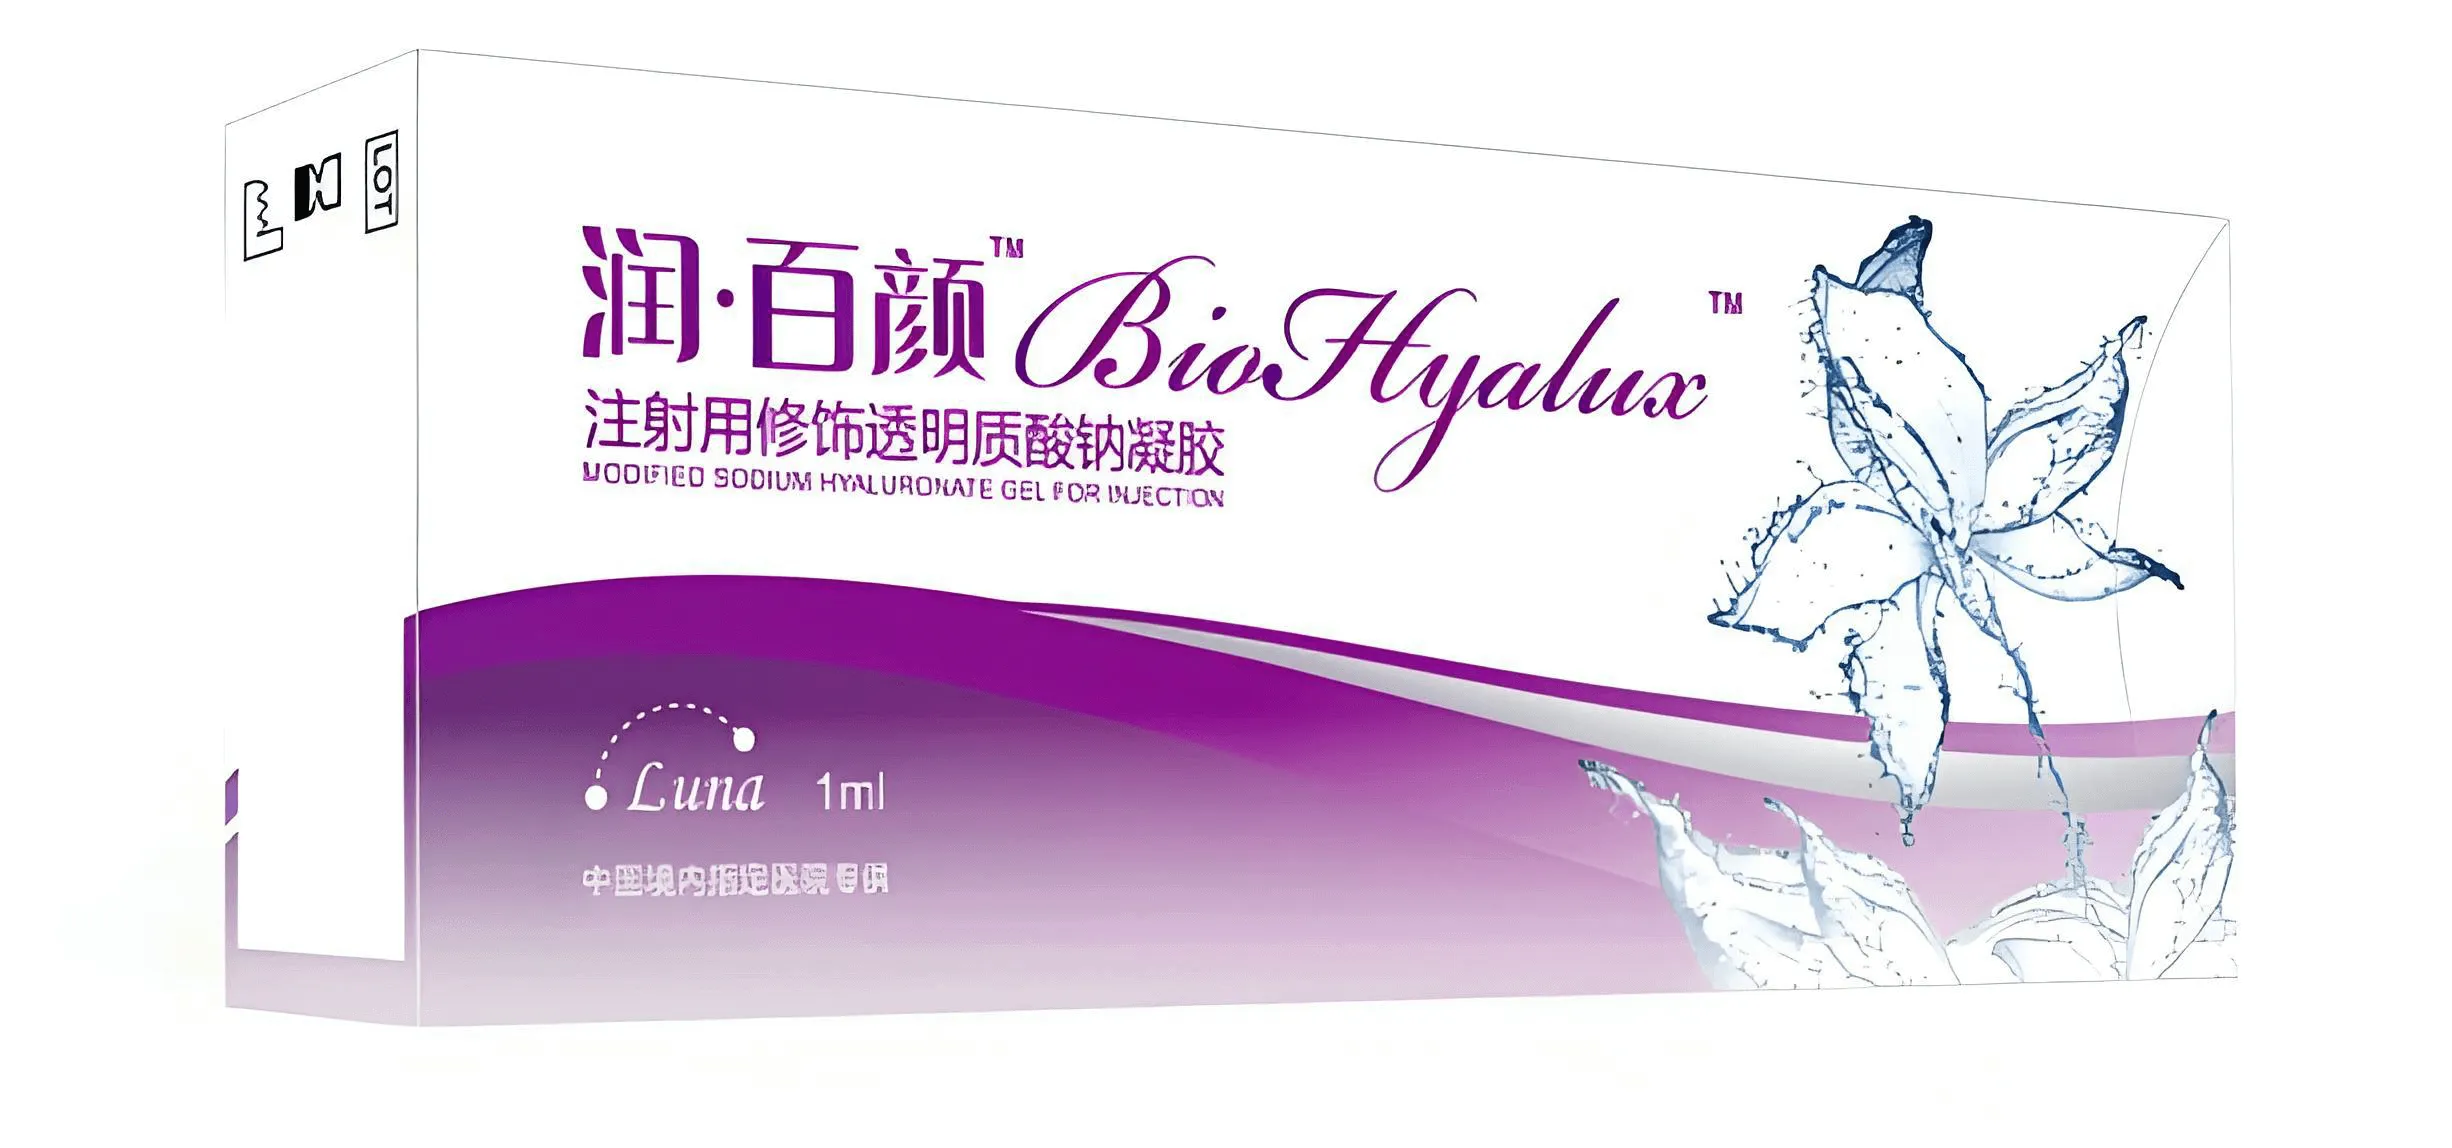

生物材料全产业链平台公司

华熙生物成立于2000年,作为一家全球领先的生物科技与生物制造企业,公司率先实现抗衰核心物质透明质酸的生物制造,市场份额常年全球第一,并以此优势为基础打开了对糖生物学和细胞生物学的前沿研究。依托公司建成的全球最大合成生物制造平台,华熙生物致力于将生命科学成果转化为应用于衰老干预、组织再生等领域的创新解决方案,目前已构建起了一个从原料到终端产品,涵盖医药、医美、营养科学和皮肤科学的整合解决方案,推出了润百颜、夸迪、米蓓尔、肌活、华熙当康等品牌。秉持“让每个生命都是鲜活的”企业使命,持续推动健康与美丽事业的发展。